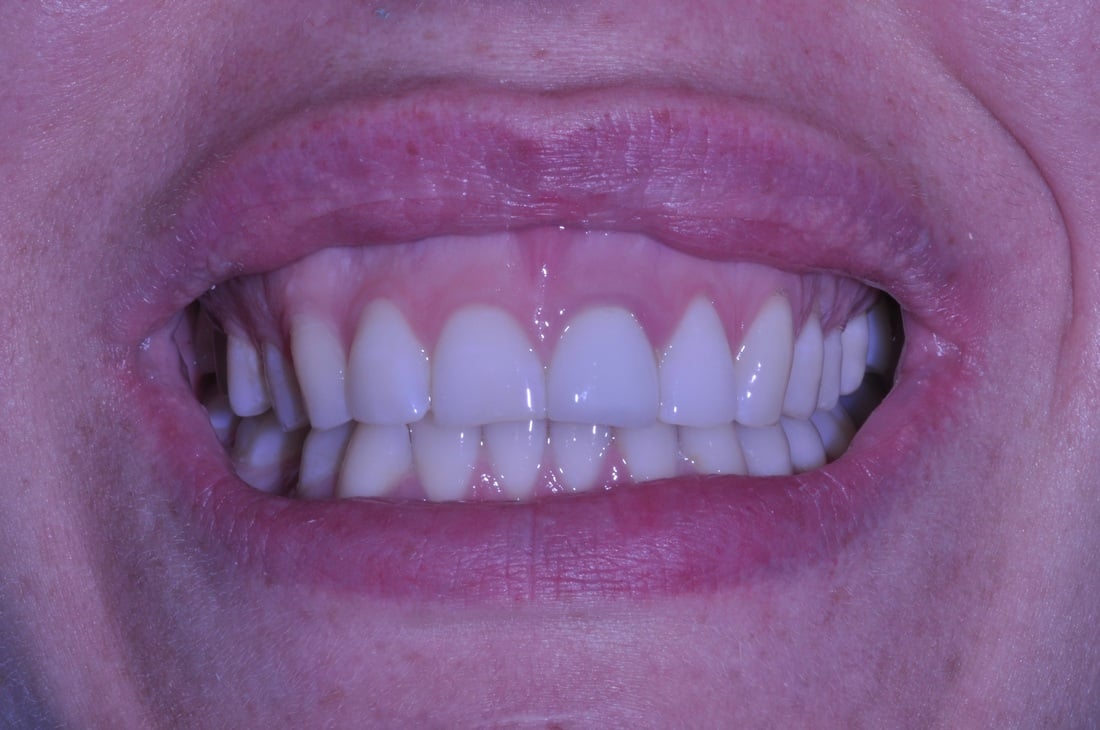

FULL MOUTH RECONSTRUCTION

This is one of the most difficult, so called “multidisciplinary” cases.

Wide spectrum of dental techniques and clinical procedures was used during this complex dental therapy. Among those were the following:

- Neuromuscular Diagnosis and Treatment of TMD-TMJ

- Dental Implants, Bone grafts & Sinus Lifts

- CAD/CAM Digital Restorative Dentistry

- Cosmetic All-ceramic Veneers, Crowns and Dental Bridges

- Teeth Extractions

- Laser Dentistry, Digital X-Rays, Virtual Smile Design

- Bio-mimetic Dentistry